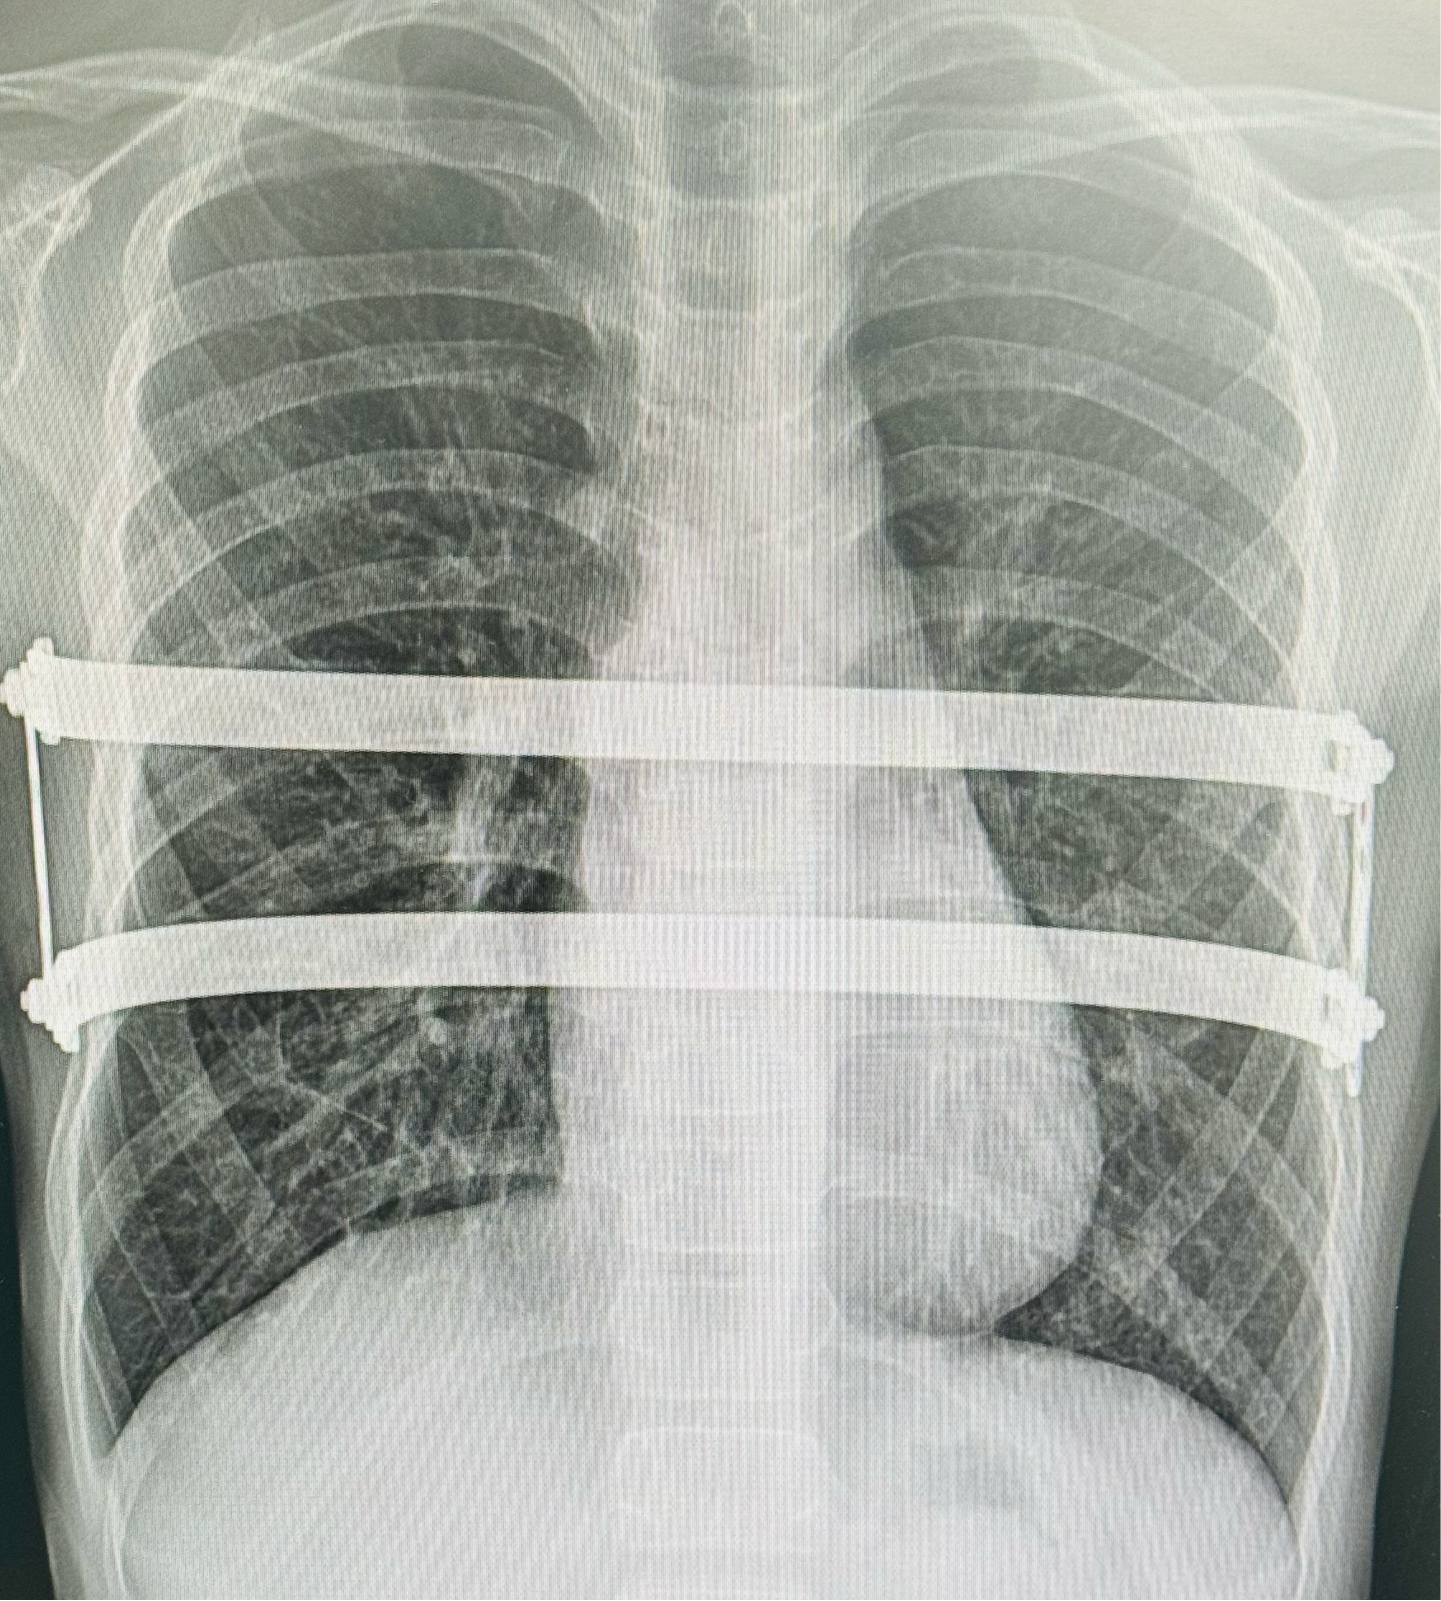

MIRPE: Revolutionizing Pectus Deformity Correction Minimally Invasive Repair of Pectus Excavatum (MIRPE) is a groundbreaking surgical technique that has transformed the treatment of pectus excavatum. This method involves placing a customized implant (bar) behind the sternum to correct the chest wall deformity. MIRPE is celebrated for its minimal scarring, faster recovery, and high success rates—over 95% in experienced hands. Success Through Precision and Quality Implants The success of MIRPE hinges on the surgeon’s precision and the quality of the implant. Using the correct implant ensures optimal chest contour, stability, and long-term results. My commitment to excellence has taken me across South Korea, China, and Thailand, where I perform pectus surgeries with the same technique, implants, and outcomes. Perfection isn’t just a goal—it’s a process I deeply believe in. Affordable and Accessible Care Advancements in pectus surgery have made MIRPE increasingly accessible and affordable, enabling patients worldwide to benefit from this transformative procedure. My mission is to deliver exceptional care and life-changing results to patients, no matter where they are. Welcome to Inhales exhales - Dedicated pectus clinic in India • Best pectus surgeon in Chennai • Top pectus excavatum specialist India • Affordable pectus excavatum surgery in Chennai • Minimally invasive pectus repair Chennai • MIRPE surgery Chennai India • Pectus deformity correction expert Chennai • High success rate pectus surgery India • Quality implants for pectus repair Chennai • Experienced thoracic surgeon Chennai • Best chest wall deformity surgeon India • Affordable minimally invasive thoracic surgery India • Life-changing pectus excavatum treatment Chennai